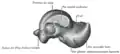

The head of talus looks forward and medialward; its anterior articular or navicular surface is large, oval, and convex. Its inferior surface has two facets, which are best seen in the fresh condition.[8]

The medial, situated in front of the middle calcaneal facet, is convex, triangular, or semi-oval in shape, and rests on the plantar calcaneonavicular ligament; the lateral, named the anterior calcaneal articular surface, is somewhat flattened, and articulates with the facet on the upper surface of the anterior part of the calcaneus.[8]

Left talus, lateral surface